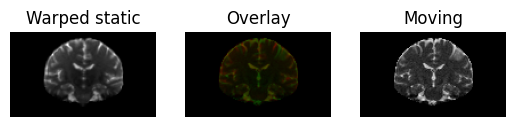

And we can also apply the inverse mapping to verify that the warped static image is similar to the moving image

warped_static = mapping.transform_inverse(static)

regtools.overlay_slices(

warped_static,

moving,

slice_index=None,

slice_type=1,

ltitle="Warped static",

rtitle="Moving",

fname="warped_static.png",

)

<Figure size 640x480 with 3 Axes>

Static image transformed under the (inverse) transformation in red on top of the moving image (in green). Note that the moving image has a lower resolution.